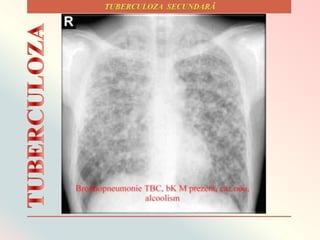

Relaţiile posibile de cauzalitate TB - consum alcool include modele specifice de

amestec social între persoanele cu tulburări de tipul consumului de alcool, ce duce la

un risc mai crescut de infecţie, sau slăbirea sistemul imunitar care să conducă la un

risc mai mare de infecţie la TB. Acesta din urmă poate avea loc direct, prin efectele

toxice ale alcoolului asupra sistemului imunitar, sau indirect, prin deficit de micro-şi

macronutrienţi, sau alte condiţii medicale legate de alcool, cum ar fi afecţiunile

maligne şi depresia (Lönnroth, 2008).